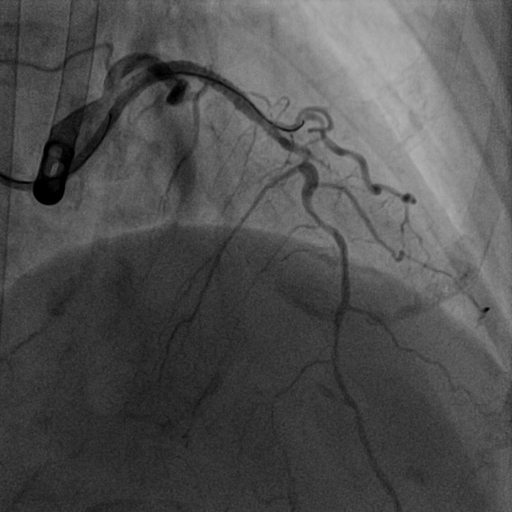

前降支介入术后图像

翟光耀主任带领高鹏副主任医师、陈文明主治医师在左室辅助装置的保护下成功对徐奶奶的前降支施行支架植入术。在经过几天康复后,徐奶奶可以正常下床活动,身体恢复良好,于近日顺利出院了。